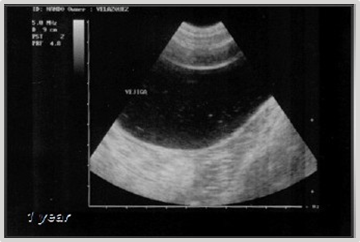

This case involves a 9-year-old female mixed-breed canine, referred for intermittent mild hematuric cystitis. Clinical examination of the abdominal cavity through palpation reveals the presence of a painless, immobile mass with a semi-soft and fixed consistency within the bladder. The ultrasonographic diagnosis reveals the presence of a heterogeneous element with irregular borders and a hypoechoic center, attached to the ventral wall and near the vesical neck, measuring 1.90 cm x 1.85 cm (Figure 1).

Figure 1 Ultrasonographic diagnosis of bladder: Heterogeneous element with irregular borders measuring 1.90 cm x 1.85 cm.